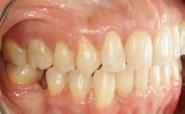

El tiempo del tratamiento fue de 2 años 11 meses, en la Figura 7 en los

estudios extraorales finales se ve la mejoría en la sonrisa y de los tejidos blandos en cuanto al perfil facial.

Estudios intraorales finales: se observa en la Figura 8 y 9 la mordida del paciente en oclusión las lineas medias coincidentes, formas de las arcadas oval, la obturacion del molar 26, la clase I canina y molar izquierda, clase I canina derecha, caracterización de premolar 14 por canino 13, clase I molar derecha y espacio en el cuandrante 4 el cual se utilizará para rehabilitación protésica.